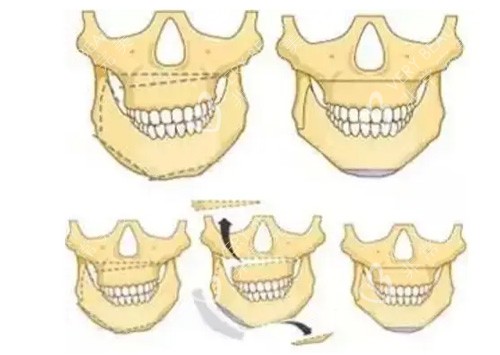

智能化术前设计:通过CT扫描获取患者颌面数据,运用3D智能系统重建三维模型,提前模拟术后结果。

例如,为一位下颌前突患者设计的手术方案,成功将下巴后推12毫米,咬合关系完全修复正常。

术中“零误差”操作:定制的3D截骨导板可精密定位截骨线,避免损伤神经和血管。

地包天矫正:22岁患者小丽因下颌前突长期自卑,何锦泉通过上下颌根间截骨术+颏成型术,将下颌骨后推至正常位置。

凸嘴修复:中年男士张先生因上颌骨前突影响职业形象,何锦泉采用上颌骨后移术,术后侧脸线条从“凸出”变为“流畅”,患者直言:“现在拍照再也不用用手挡下巴了。